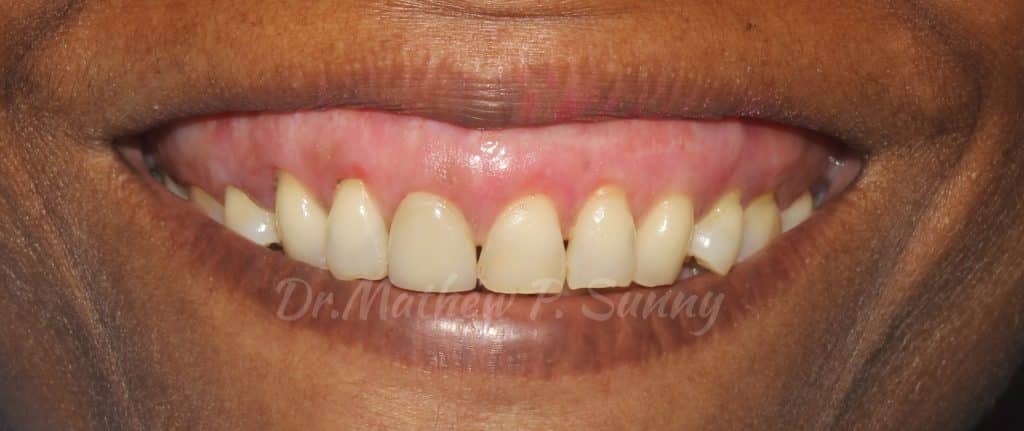

Initial presentation of smile showing significant high smile line and melanin pigmentation of the tissues..